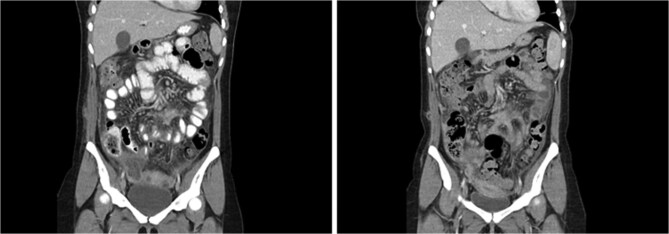

卵巢皮样囊肿,或成熟囊性畸胎瘤,是常见的良性卵巢肿块。对症状性囊肿的手术干预包括微创或开放性囊肿切除术。膀胱切除术中腹腔内溢液的后果可能很严重,包括急性化学性腹膜炎或慢性肉芽肿性炎症反应。这是首例报道的腹膜切除术治疗弥散性皮样疾病的病例。本病例报告讨论了一位健康的20岁患者在选择性腹腔镜卵巢囊肿切除术后出现这两种并发症。她需要多次入院和多学科的方法来制定治疗计划,最终进行了腹膜切除术。该病例需要重要的多学科讨论,以解决有关抗菌和手术管理的复杂治疗决策。这是首例报道的腹膜切除术用于控制播散性皮样病后慢性脓毒症和肉芽肿性腹膜炎的病例,强调了及时干预和彻底腹膜冲洗对减轻晚期炎症并发症的重要性。

Dermoid ovarian cysts, or mature cystic teratomas, are common benign ovarian masses. Surgical intervention for symptomatic cysts includes minimally invasive or open cystectomy. The consequences of intra-abdominal spillage during cystectomy can be significant and include acute chemical peritonitis or chronic granulomatous inflammatory reactions. This is the first reported case of peritonectomy for disseminated dermoid disease. This case report discusses a previously healthy 20-year-old patient who developed both these complications following elective laparoscopic ovarian cystectomy for dermoid ovarian cysts. She required multiple admissions and a multi-disciplinary approach to develop a treatment plan, culminating in peritonectomy. This case necessitated significant multi-disciplinary discussion to address complex treatment decisions regarding anti-microbial and surgical management. This is the first reported case of peritonectomy for source control of chronic sepsis and granulomatous peritonitis following disseminated dermoid disease, highlighting the importance of timely intervention and thorough peritoneal wash-out to mitigate late inflammatory complications.